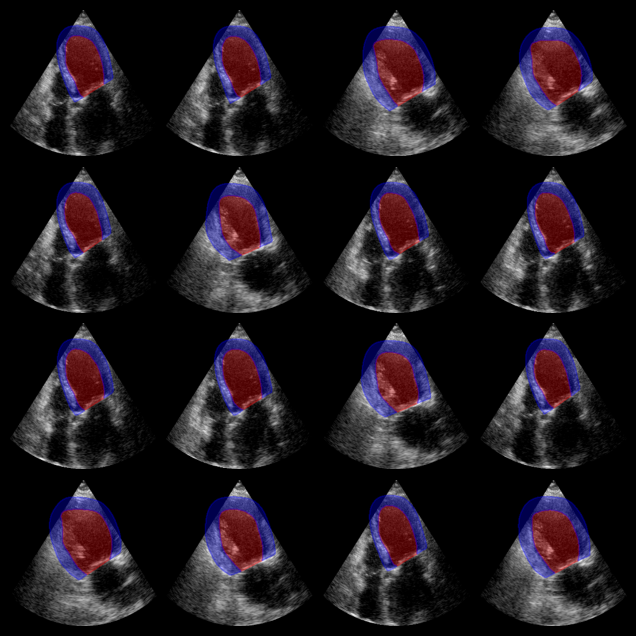

EchoNetDynamic segmentation results:

The red overlay shows the predicted left ventricle mask for each image.

EchoNet-Dynamic Example Output

Now we use the Augmented CAMUS nnU-Net model, which segments both the left ventricle and myocardium (2 labels). The model expects input in NCHW format (batch, channels, height, width).

# Visualization: show both LV (label 1) and myocardium (label 2)

plot_shape_from_mask(ax, mask == 1, color="red", alpha=0.3)

plot_shape_from_mask(ax, mask == 2, color="blue", alpha=0.3)